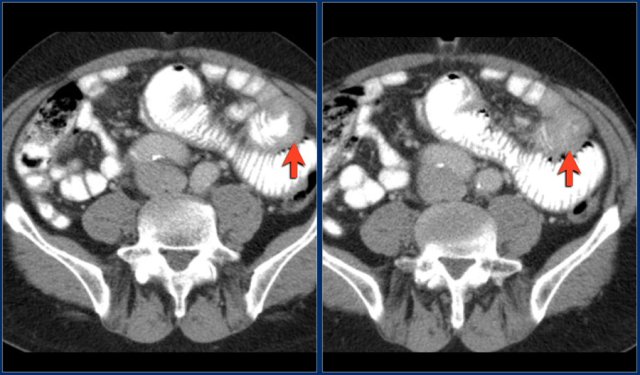

The images show a short obstructing circular mass in the jejunum (yellow arrow) with enlarged lymph node (red arrow).

This proved to be an adenocarcinoma.

The red arrow indicates the sigmoid, which is filled with feces. So this is not a small bowel feces sign.

The findings are:

- Obstructing lesion in the ileum with shouldering leading to small bowel obstruction (yellow arrow).

One could consider the diagnosis of Crohn's disease.

However this patient was not known with Crohn's disease and the terminal ileum (not shown) was normal, which would be uncommon.

At surgery this proved to be an adenocarcinoma.